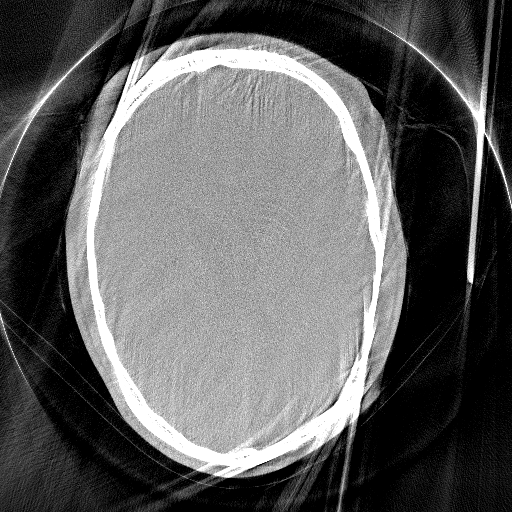

We use Adam optimization with learning rate of 0.000010.000010.00001 and select the network parameters that achieved the best RPE prediction on our validation dataset. Our network achieves an average RPE deviation from the Gt of 0.0310.0310.031 mm on the test dataset, as depicted in Fig. 1.

Figure 1: Network estimated RPE and different reconstructions, all revealing a RPE of 0.34absent0.34\approx 0.34 mm.